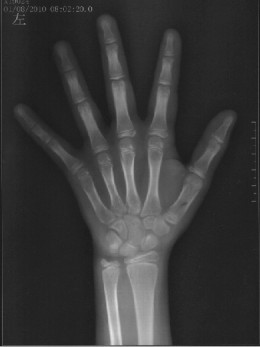

骨龄是孩子生长发育的“生物时钟”,比实际年龄更能反映身高增长潜力。本次义诊将通过左手腕部X光片精准测评骨龄,科学预测成年终身高,排查生长迟缓、性早熟等潜在问题。

辐射剂量极低:本次活动,徐州一院将运用智能化的专用骨龄仪评测骨龄,辐射量微小,相当于阳光下漫步20分钟的太阳辐射。新一代骨龄仪从拍照到生成骨龄结果仅需1分钟,智能生成骨龄结果,让测骨龄和量血压一样简单!

评估标准权威:采用《中华-05》骨龄评价方法,贴合中国儿童发育特点,结果精准可靠。